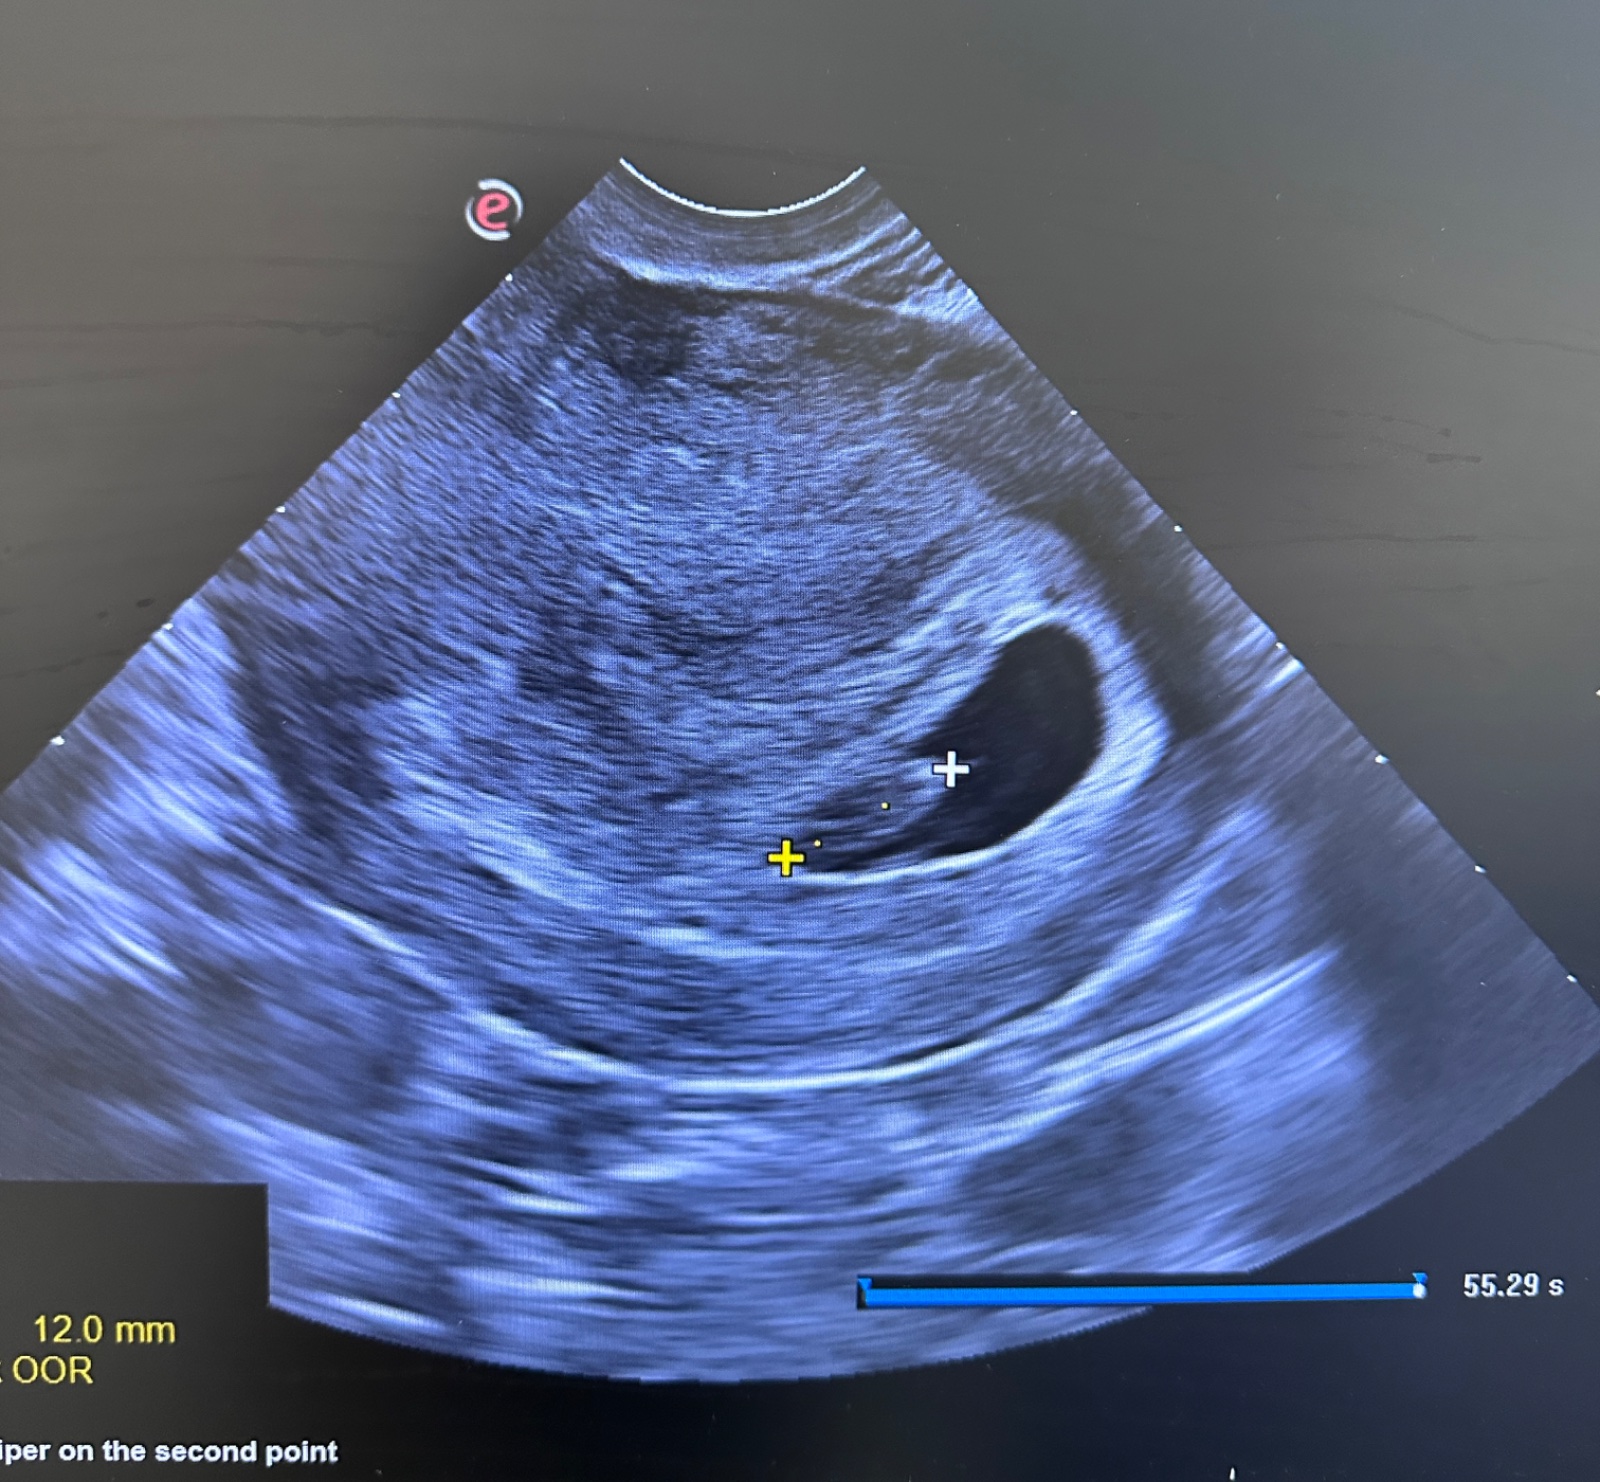

@mony970 ahoj pošlem ti fotku môjho sona 7+3 pre predstavu . Podľa mňa keby to bolo zle tak by ti to hneď povedala 🙂 🫶🏻